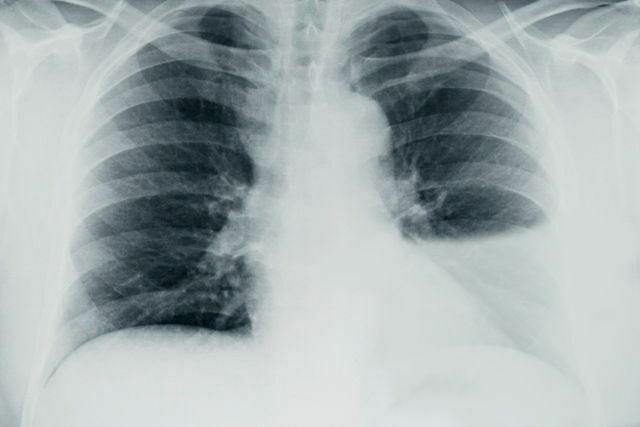

O que esse raio x sugere e quais são as os sinais presentes? Derrame pleural; Imagem em menisco, parabola de Demousiau, opacificação do espaço pleural, deslocamento do diafragma, imagem em menisco, fissuras pleurais e leve deslocamento do mediastino.

Quais são os achados radiológicos do derrame pleural? O que pode causar a doença? -Presença de muito líquido no espaço pleural -Obliteração do seio costofrênico (preenchimento do espaço entre as costelas e o diafragma) -Imagem em menisco -Elevação da cúpula diafragmática -Lawrell pode deslocar o líquido; Tuberculose e neoplasias (Doença pleural), insuficiência cardíaca e congestiva (Doença sistêmica)